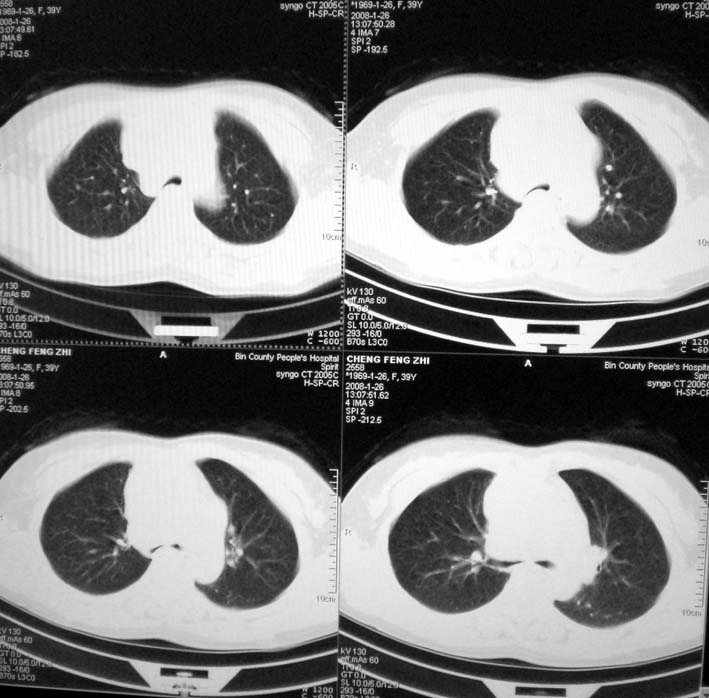

以下是引用guoke在2008-1-27 14:15:00的发言:[br]纵隔增宽,纵隔内血管境界不清,心包积液,考虑纵隔淋巴瘤.[br]

以下是引用随光逐影在2008-1-27 15:52:00的发言:[br]1)考虑为:淋巴瘤。建议:行进一步检查。2)心包积液。